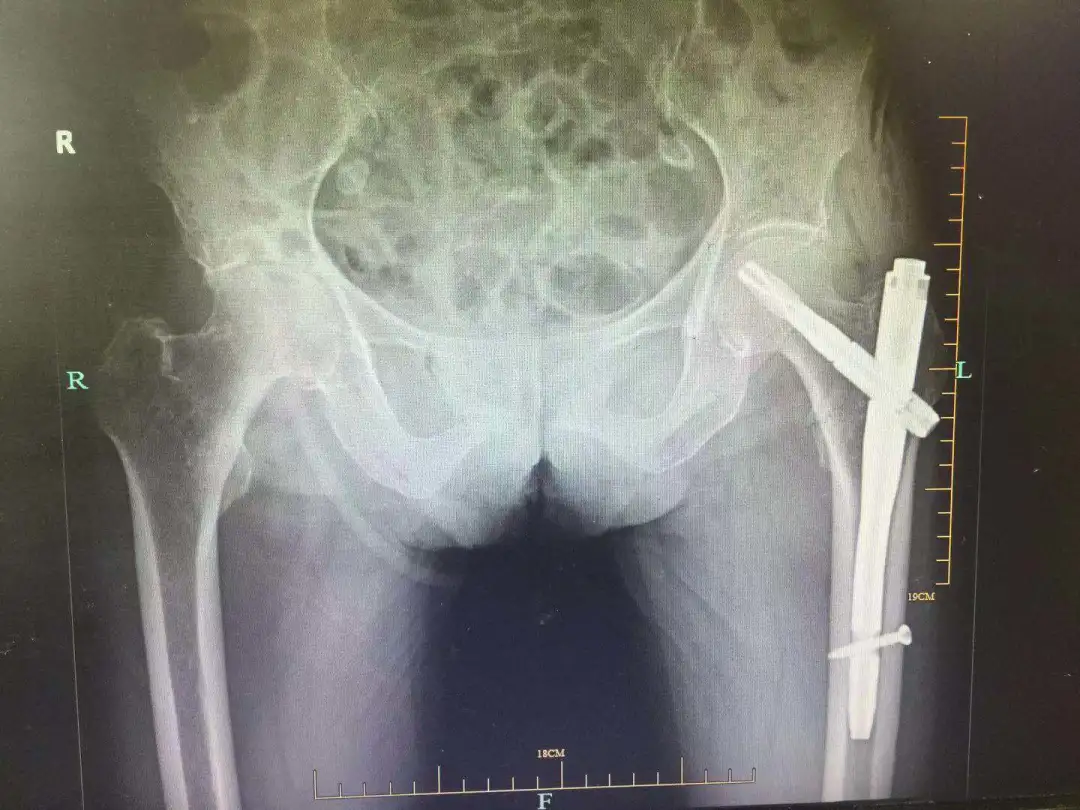

87 岁宋奶奶术后影像学资料

最终,骨科、麻醉科、手术室团队分别为三位老人成功实施了「股骨粗隆间骨折 PFN-A 固定术」(微创手术),平均用时 30 分钟,创伤小、出血少、恢复快,用尽可能短的时间保障医疗安全,降低手术风险。